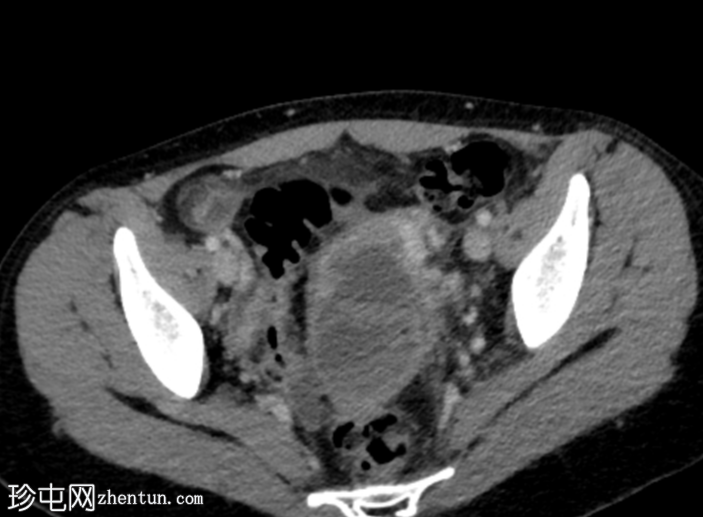

轴位增强扫描(门静脉期)

左侧附件可见多房性管状、迂曲囊性病变,囊壁不规则增厚,内部可见碎屑和分隔,符合输卵管积脓的诊断。左侧卵巢未单独显示。

盆腔少量腹水,盆腔腹膜脂肪间隙轻度模糊。

右侧卵巢可见一小黄体囊肿,边缘增厚并有强化。

子宫周围静脉通道明显,提示轻度盆腔充血综合征。

典型的放射学特征如本例所示,包括管状多房性复杂附件病变,伴有碎屑、分隔和不规则的厚壁,这可以确诊为输卵管积脓。